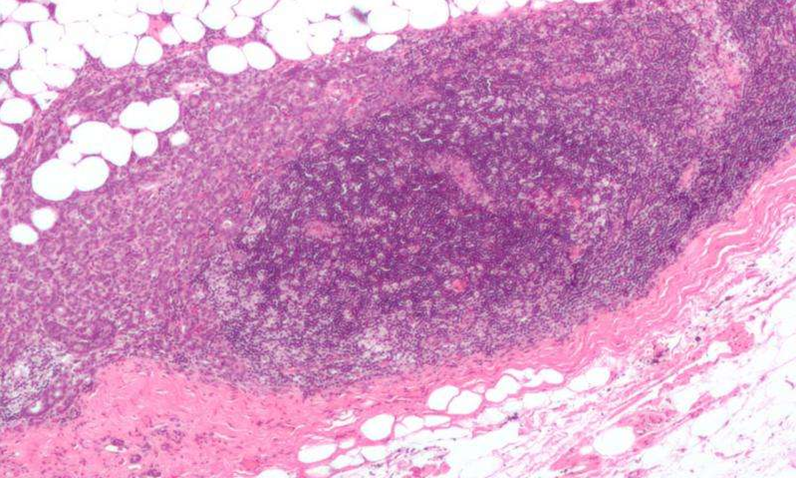

近日,刊登在国际闻名杂志Cell上的一项研究报告中,来自纽约大学医学中心(NYU Langone Medical Center)的科学家通过对乳腺癌细胞功能的大量分析,揭示了当前许多药物的新用途,以及用于药物开发和组合性药物开发的新靶点;同时也可以帮助科学家们寻找其它种类癌症的新型候选药物,为揭示癌症耐药性的产生也提供了新的思路。

相比以往研究而言,研究人员对多种类型的乳腺癌细胞进行了组合性的遗传分析,Benjamin Neel博士表示,这项研究阐述了一种新的研究思路,即揭示了乳腺癌细胞的遗传改变如何干扰对癌细胞生长和生存关键的通路,而这种通路或许可以被当前存在的多种药物的组合进行靶向作用。研究者利用新型的统计学方法对早期技能进行了改进,其可以帮助鉴别出对特殊乳腺癌亚型非常关键的多种基因,比如HER2、雌激素受体/ER、HER3等。

研究人员对77份乳腺癌细胞系进行了shRNA的筛查研究,而这些样本的研究足以阐述多种乳腺癌亚型,随后研究者利用新型的统计学技能,即si/shRNA混合效应模型(siMEM)技能,来对细胞系基因敲除研究进行评分,较终鉴别出对癌症生长重要的候选基因;同时研究者还可以将研究结果同癌症遗传数据库的信息进行对比。